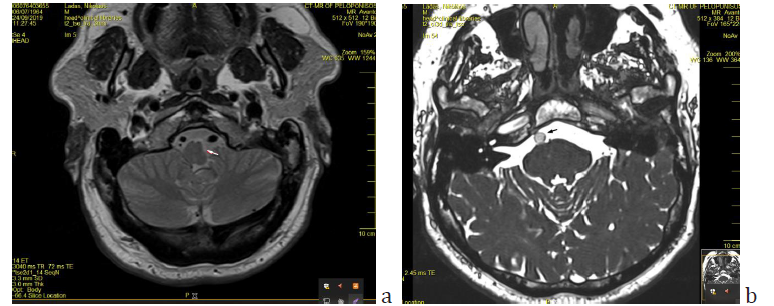

Figure 2: Brain CT scan of the patient sixteen years before the first episode of SSNHL, when he had a car accident. a) The enlargement and beginning tortuosity of the left vertebral artery is evident (arrow). b) The basilar artery has already a lateralized position at the right border of the dorsum sellae but it does not appear enlarged.

Sixteen years before the first episode, the patient had had a car accident for which he had a brain CT scan which was otherwise normal apart from an incidental comment about the existence of a tortuous left vertebral artery (Figure 2). MRI imaging findings of the vertebrobasilar segment are shown on Figures 3 & 4.

One of the unique features of the present study is the existence of an imaging modality sixteen years before the occurrence of SSNHL. Although it is not an MRI but a CT, the finding of a tortuous left vertebral artery had been pinpointed even at that time of the past. The basilar artery appeared lateralized at the level of upper pons but no ectasia was apparent yet at that time. In none of the relevant studies has there been a previous imaging report to testify the longevity and/or the pathogenesis of VBD. The asymmetric vertebral artery flow contributes to the development of basilar artery curvature in the side opposite to the side of VA dominancy. There are references about the existence of a dominant vertebral artery more frequently on the left side [18-20]. Despite the fact that hyperlipidemia and hypertension were present in the patient’s recent medical history, (of a few years) the lateralization of the BA being evident many years earlier (Figure 2b) is in accordance with the pathogenetic theory of a mechanism other than atherogenesis, involving a disfunction of matrix metalloproteinases leading to aberrant vascular remodeling and abnormal connective tissue in the arterial wall [3,22].